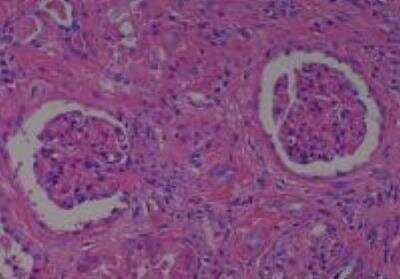

Hematoxylin & Eosin Stain: Human Common Tissue MicroArray (Normal Adjacent) [NBP2-30215] - 103. Stomach